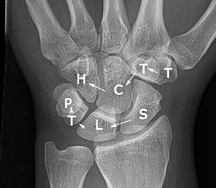

Figure 3: PA wrist

When evaluating the PA view of the wrist (Figure 3), the joint spaces of the wrist have a width of 2 mm or less. Only the radiocarpal joint is slightly wider. The carpometacarpal joints are slightly narrower than the midcarpal joints. The capitolunate joint is considered the baseline joint width to which other joint spaces can be compared. Make sure to look at all of them: the radiocarpal, the proximal intercarpal, the midcarpal, the distal intercarpal and the carpometacarpal joint spaces.

Figure 5: The carpal bones: scaphoid, lunate, triquetrum, pisiform, trapezium, trapezoid, capitate and hamate

Can you remember the names of all the carpal bones? You've got the scaphoid, lunate, triquetrum, pisiform, trapezium, trapezoid, capitate and hamate. (Figure 5)